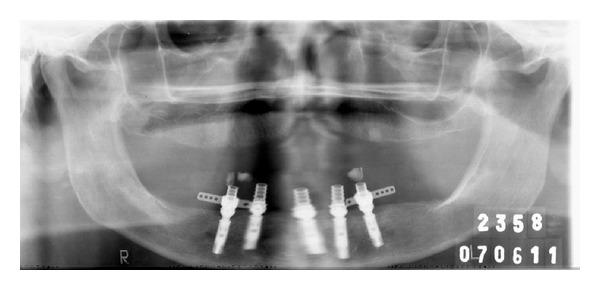

In mandibular edentulous patients, treatment based on immediate loading with rigid splinting in the mandible is well accepted; however, it is cost and time dependent, which sometimes limits this type of rehabilitation. To overcome these problems, the technique of immediate loading using a semirigid splinting extension system has been developed. Its advantages include low cost, technical feasibility, and reduced clinic time. This clinical report presents the applicability and the predictability of semirigid splinting of implants in the mandibular arch of an edentulous patient using a distal extension bar prosthesis system.

在下颌无牙患者中,基于下颌即刻负重并采用刚性夹板固定的治疗方法已被广泛接受;然而,这种方法成本较高且耗时,有时会限制此类修复方式的应用。为克服这些问题,已开发出使用半刚性夹板延伸系统进行即刻负重的技术。其优点包括成本低、技术可行性高以及临床时间缩短。本临床报告介绍了在一名无牙患者的下颌弓中使用远端延伸杆假体系统对种植体进行半刚性夹板固定的适用性和可预测性。